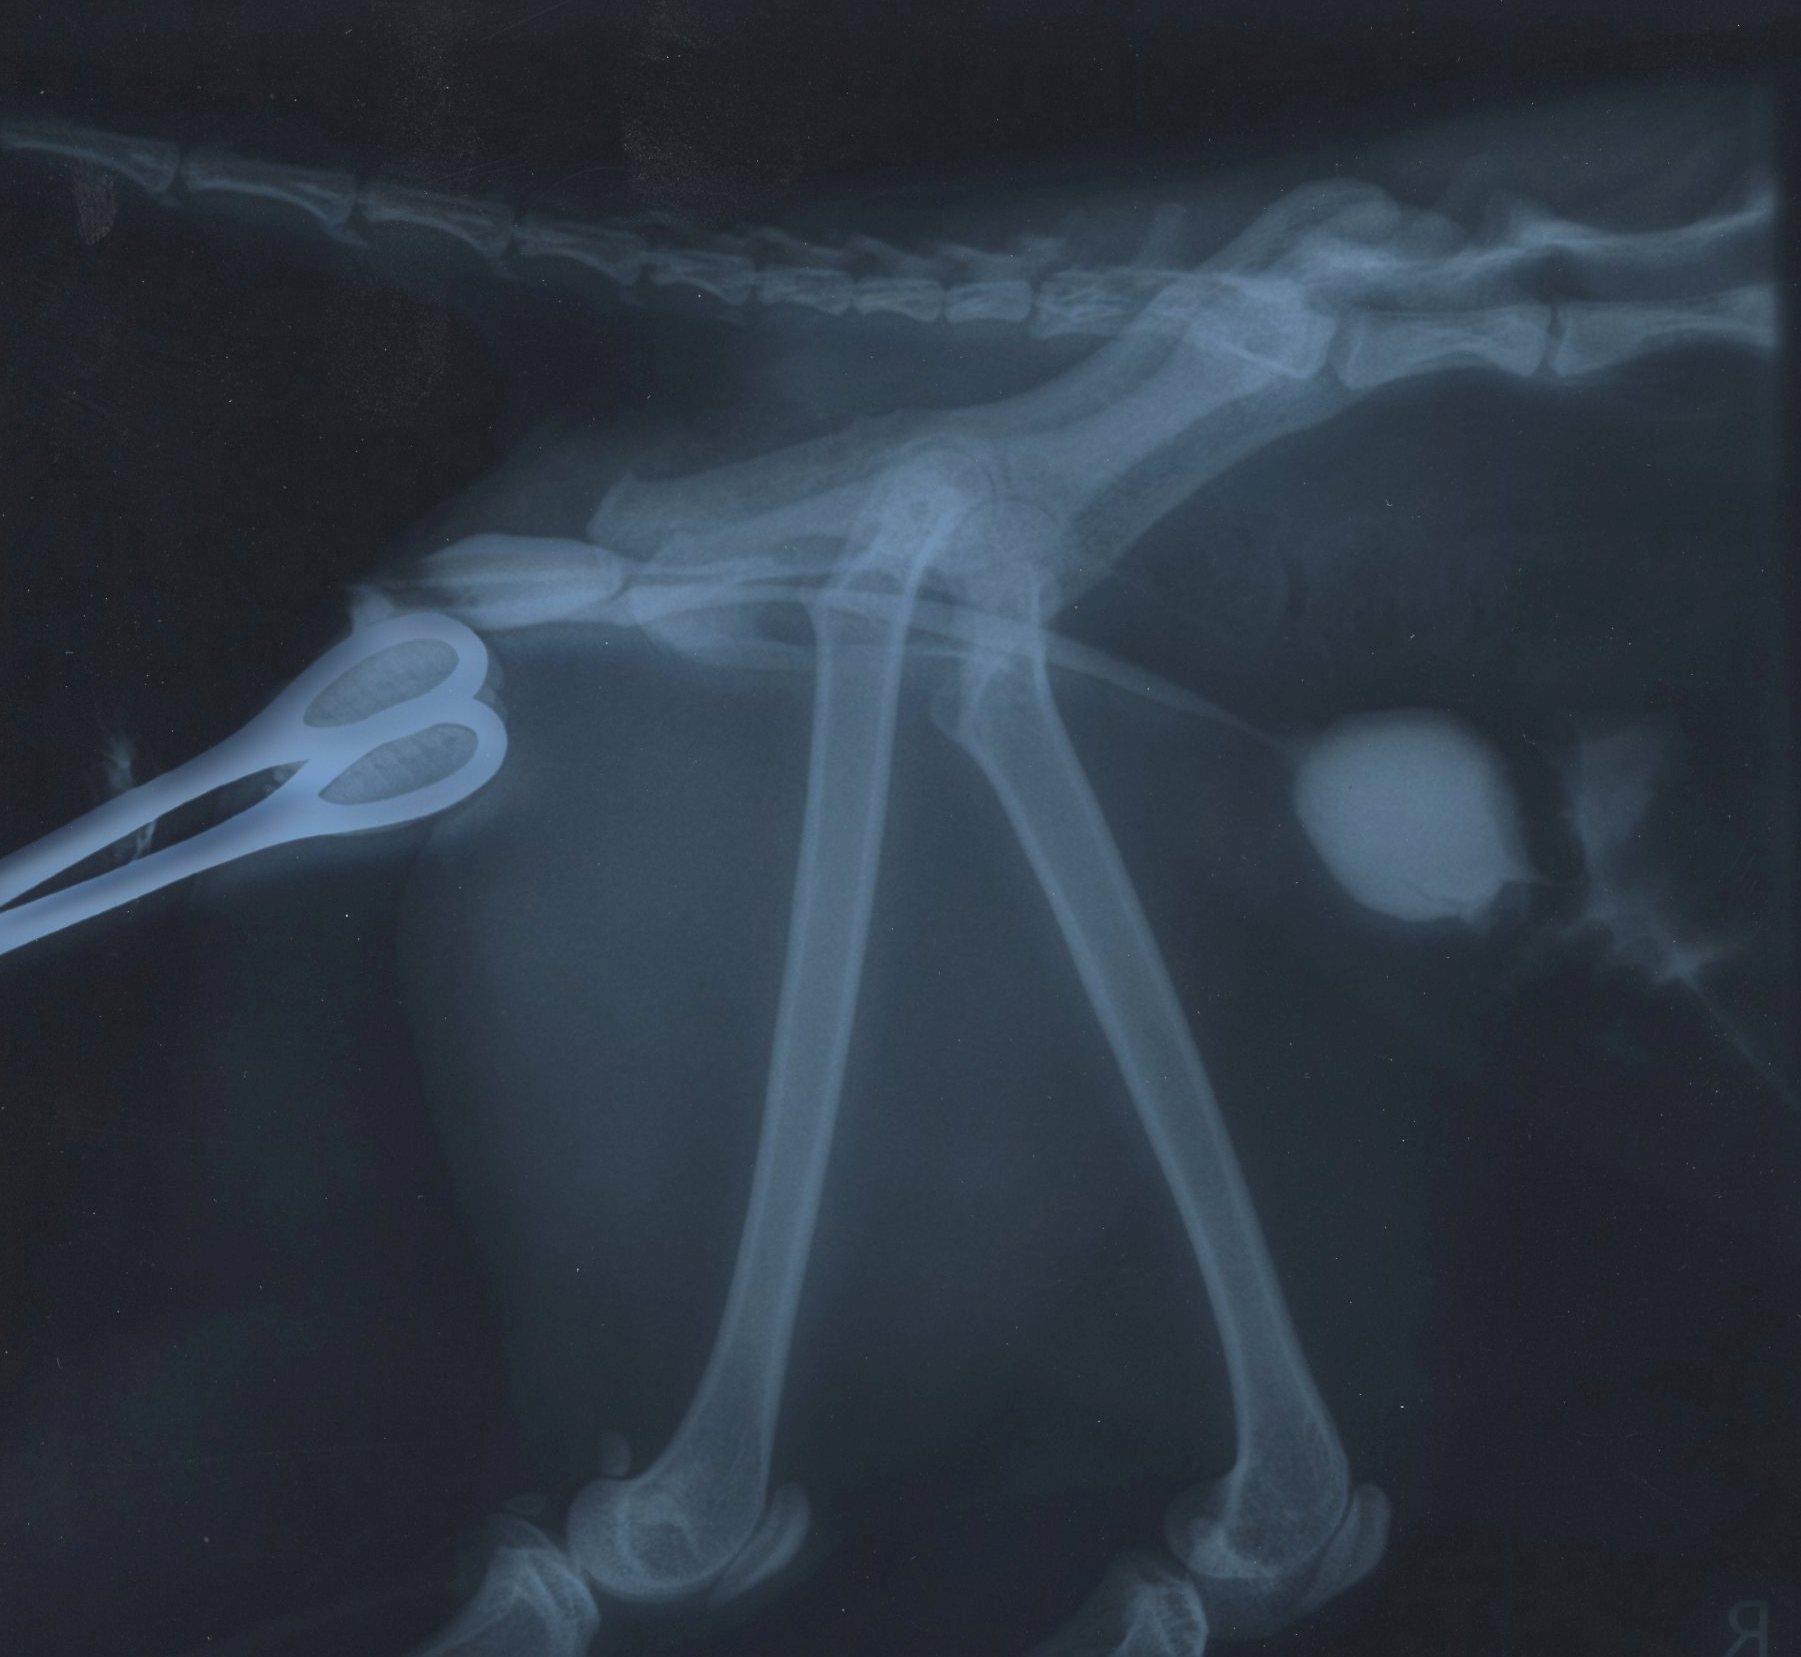

Urine can leak from the renal pelvis, ureters, urinary bladder and proximal urethra. The terminal intrapelvic urethra (and further distal) are extra abdominal and shouldn't cause peritoneal effusion. They can cause marked bruising and, more chronically, skin sloughing. To determine the location of the leak, retrograde positive contrast urethrocystography is a simple and accurate test if performed properly. Images are obtained whilst contrast is instilled at the penis; it is a dynamic study and instilling contrast followed by a pause before taking the radiograph can introduce artefact or fail to properly dilate the lower urinary tract.

This dog had bilateral sacroiliac luxurious, accounting for the musculoskeletal signs. He responded to treatment for pain and hypovolaemia. He had a traumatic bladder rupture that was repaired primarily once he was stable for anaesthesia.